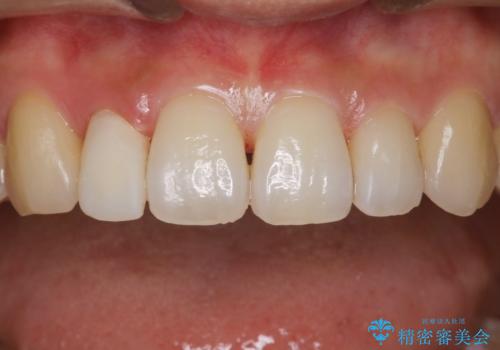

- 治療計画

- インビザラインで矯正中の患者様です。リファインメントのタイミングでホームホワイトニングをご希望でしたが、歯の表面にステインがかなり付着していたため、エアフローでのクリーニングからお勧めしました。

歯の表面にステインやバイオフィルムが付着していると、歯面がざらつき更に汚れが付きやすくなるだけでなく、付着物の影響でホワイトニング薬剤の浸透が悪くなりトーンアップ効果が減少します。歯の表面の汚れを落とすことで歯面もツルツルになり、ホワイトニングを行わなくても歯が白くなった様に感じられる場合もあります。

エアフローだけで歯が白くなったと喜んでいらっしゃいました。新しいマウスピースが届くまでの間はホームホワイトニングを行い歯の内部から白くしていきます。